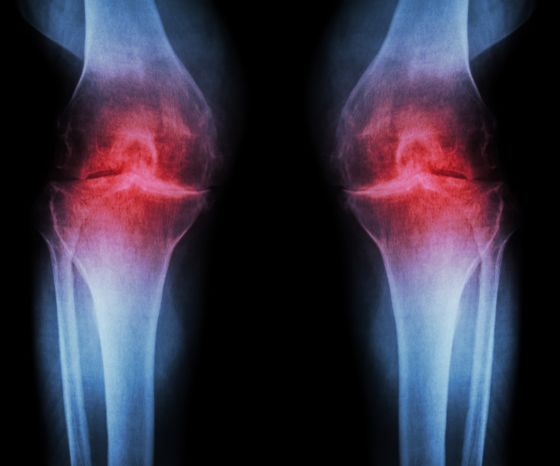

Klasickým znakom osteoartrózy kolena sú histologické zmeny kvality a hrúbky kĺbovej chrupavky. Úbytok kĺbovej chrupavky vedie k hypertrofii subchondrálnej kosti a tvorbe osteofytov na okrajoch kĺbových plôch. Ďalším dôsledkom je chronický zápal synoviálneho tkaniva. Všetky tieto zmeny vedú k nepravidelnému povrchu kĺbov, zväčšeniu kostí, možnému zhrubnutiu kĺbového puzdra a nakoniec k hydropsu. Výsledné zmenšenie kĺbového priestoru je viditeľné na röntgenových snímkach, preto hovoríme aj o "rádiologickej osteoartróze".

Najčastejšie používaným klasifikačným systémom pre rádiologickú osteoartrózu je Kellgrenova a Lawrencova stupnica(Kohn a kol. 2016):

- Stupeň 0: nie sú prítomné žiadne rádiografické znaky OA

- Stupeň 1: pochybné zúženie kĺbového priestoru a možné osteofytické obrvenie

- Stupeň 2: definitívne osteofyty a možné zúženie kĺbového priestoru na predozadnom RTG snímku pri zaťažení

- Stupeň 3: početné osteofyty, určité zúženie kĺbového priestoru, skleróza, možná kostná deformita

- Stupeň 4: veľké osteofyty, výrazné zúženie kĺbového priestoru, závažná skleróza a definitívna kostná deformita